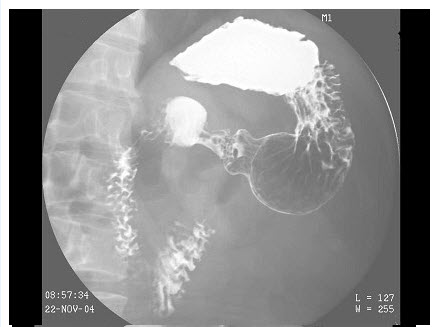

5、单项选择题

男,40岁,黑便1周,半年来呕血两次。查体:脾肋下4cm,结合图像,最可能的诊断为()

A.正常食管

B.食管癌

C.食管静脉曲张

D.贲门癌

E.食管炎

点击查看答案